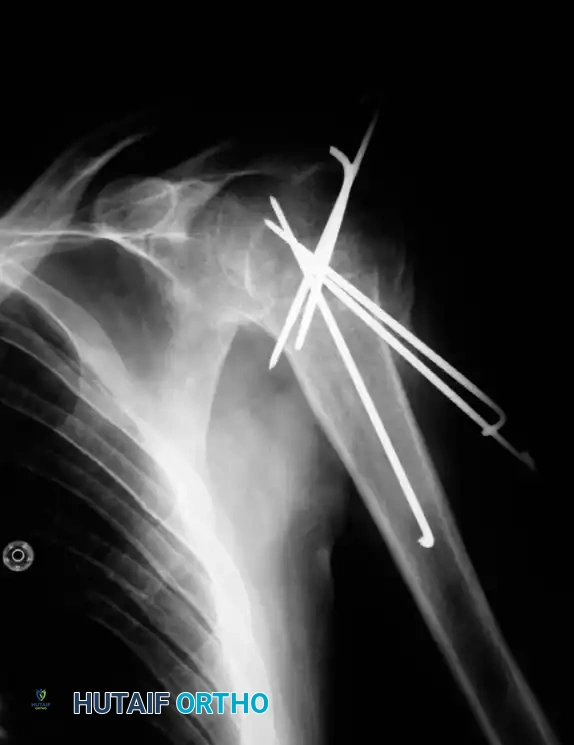

Percutaneous Pinning

Percutaneous pinning offers the distinct advantage of avoiding extensive soft-tissue dissection, thereby maximally preserving the blood supply to the humeral head. It is a minimally invasive, cost-effective technique. Jaberg et al. and Resch et al. have reported excellent outcomes using threaded pins or Kirschner wires.

Technique Overview:

* Closed reduction is achieved under fluoroscopy using traction, abduction, and manipulation.

* Pins are introduced percutaneously from the lateral humeral cortex, directed superomedially into the humeral head.

* Additional pins may be placed anteriorly to secure the lesser tuberosity or superiorly for the greater tuberosity.

* Warning: The axillary nerve is at risk during lateral pin insertion. Pins must be placed carefully, often utilizing a small stab incision and blunt dissection to the bone.